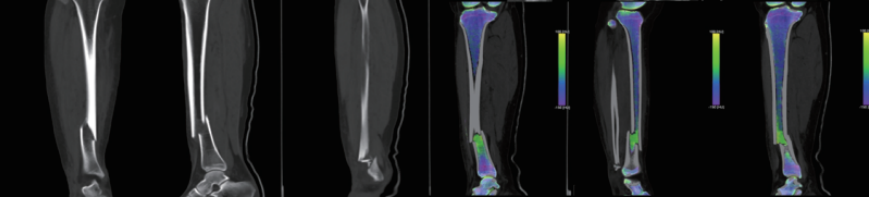

案例圖

骨 髓 顯 像